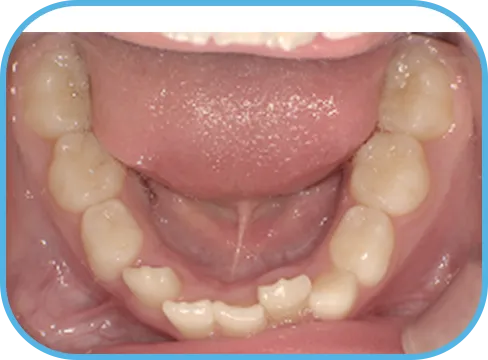

• 下 顎

治療前下顎からの歯の様子